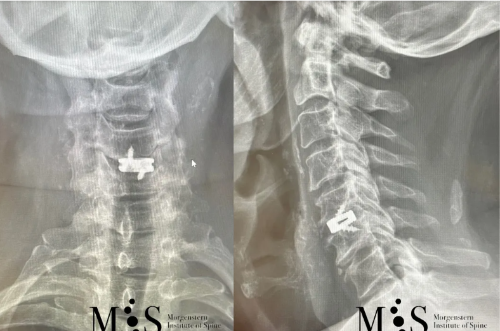

X-ray in A/P (left figure) and lateral (right figure) figures of a titanium

interbody cage placed at level C5/C6 with endoscopic surgery